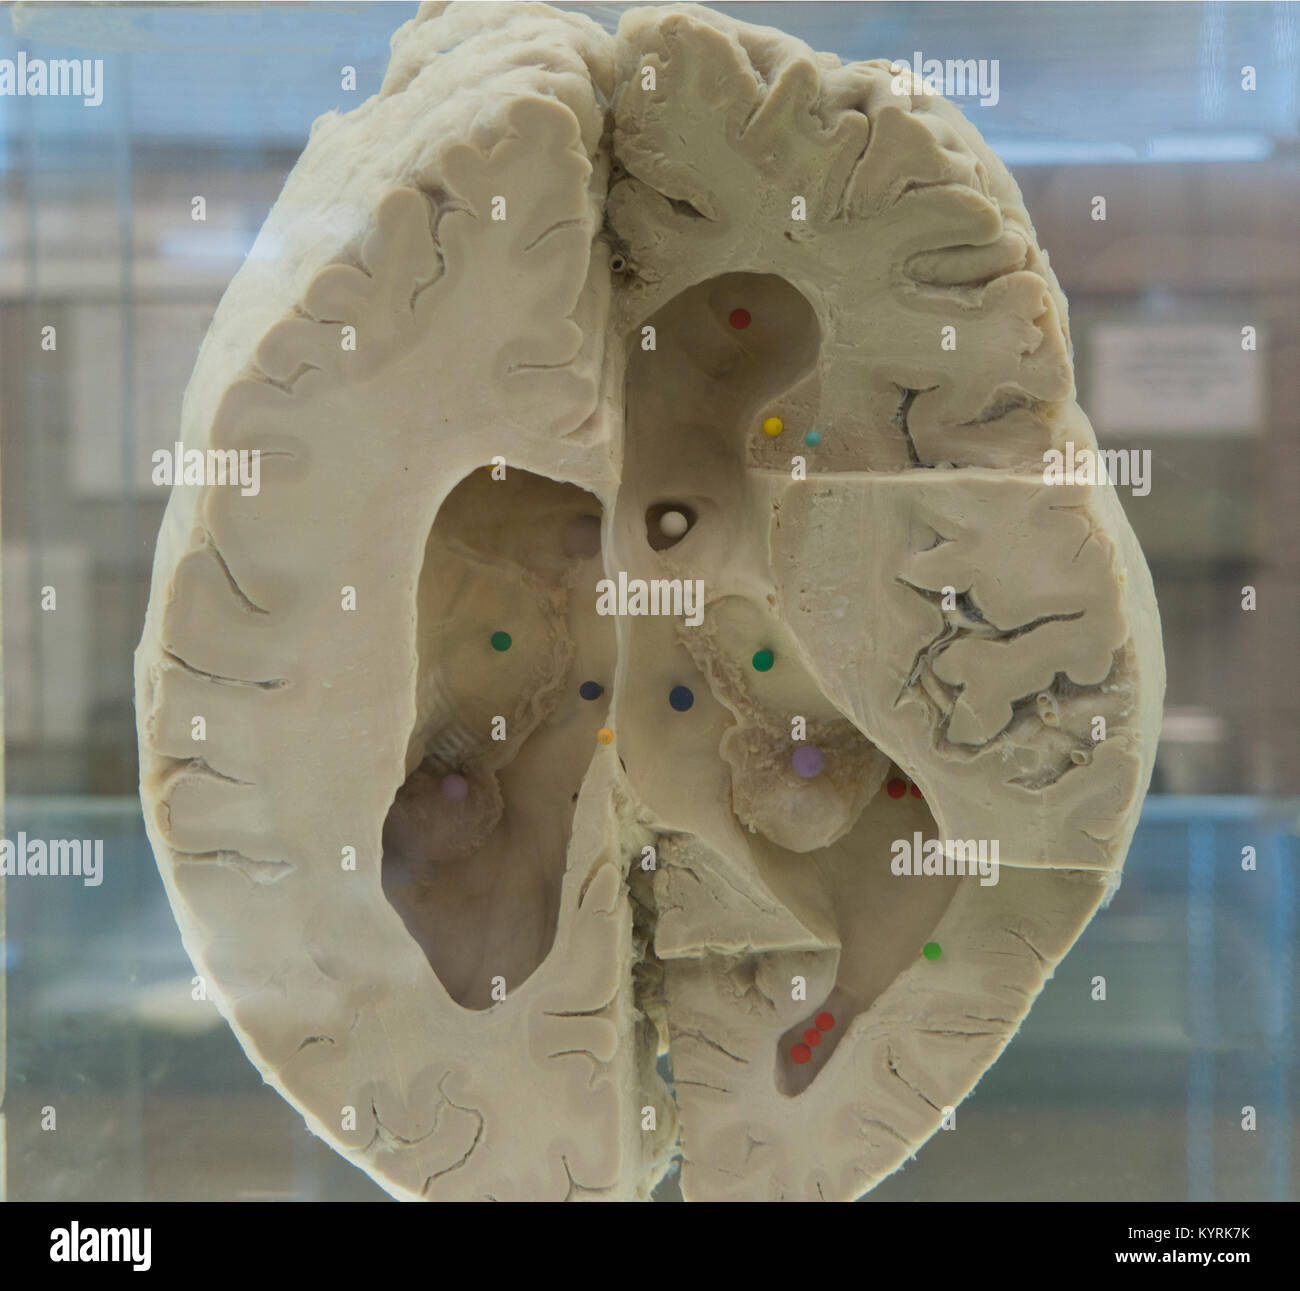

RMBCE641–Sagittale Abschnitt des menschlichen Gehirns, Darstellung von Strukturen der zerebralen Ventrikel, Kleinhirn und Hirnstamm.